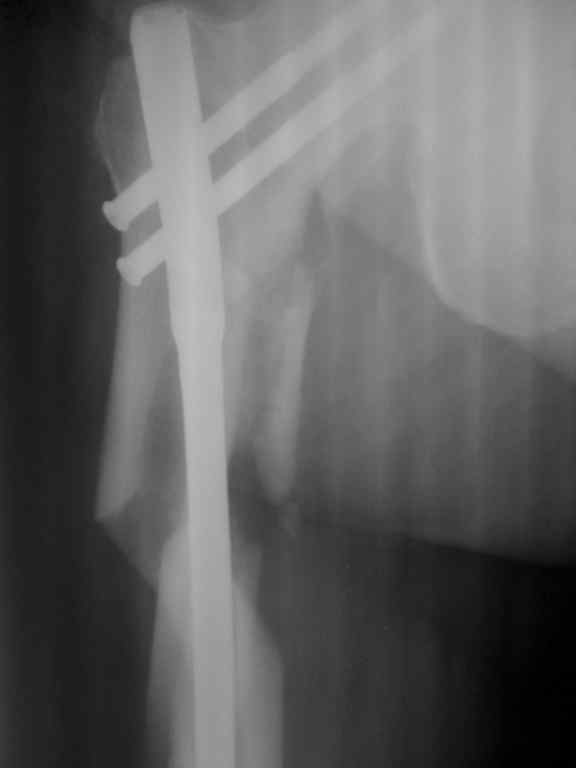

Р-гр после операции

|

Что то по представленным рентгенограммам не пойму, что же произошло. Ножка вне диафиза, но как она вышла из канала? Даже странно.

такое впечатление, что штифт сломался на 2-ом проксимальном винте и таким образом послужил распоркой между проксимальным и дистальным отломками (линия перелома была косая, насколько я понимаю)